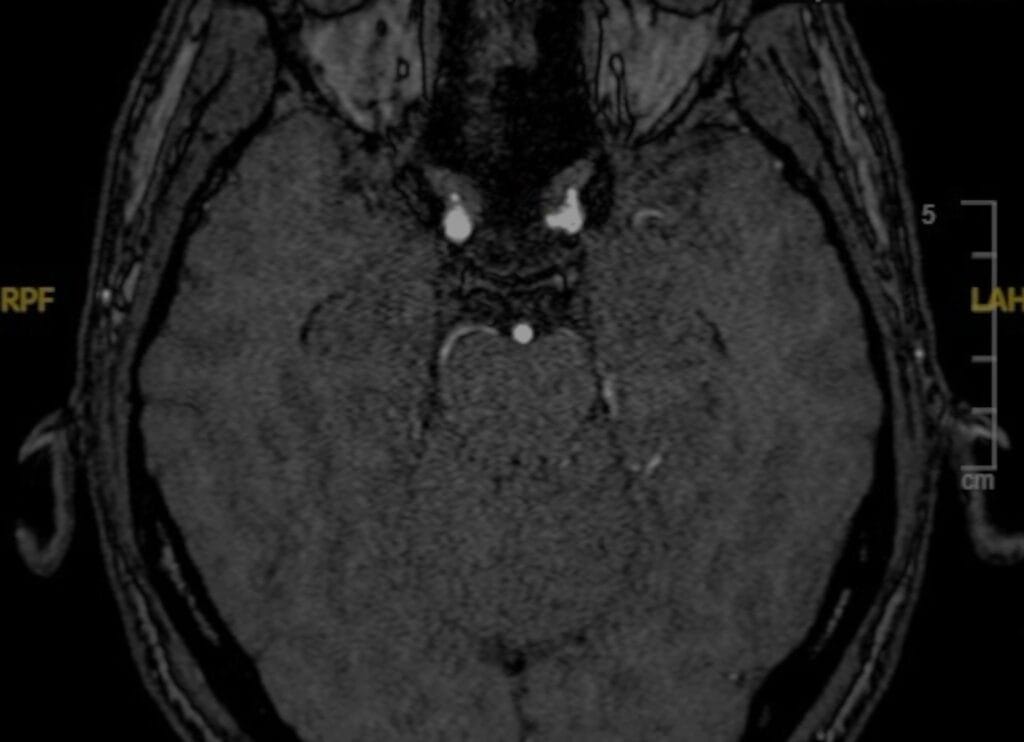

Clipaje microquirúrgico de aneurisma basilar

El Dr. Luis Borba realiza el clipaje microquirúrgico de un aneurisma grande en la punta basilar en una paciente de 67 años.